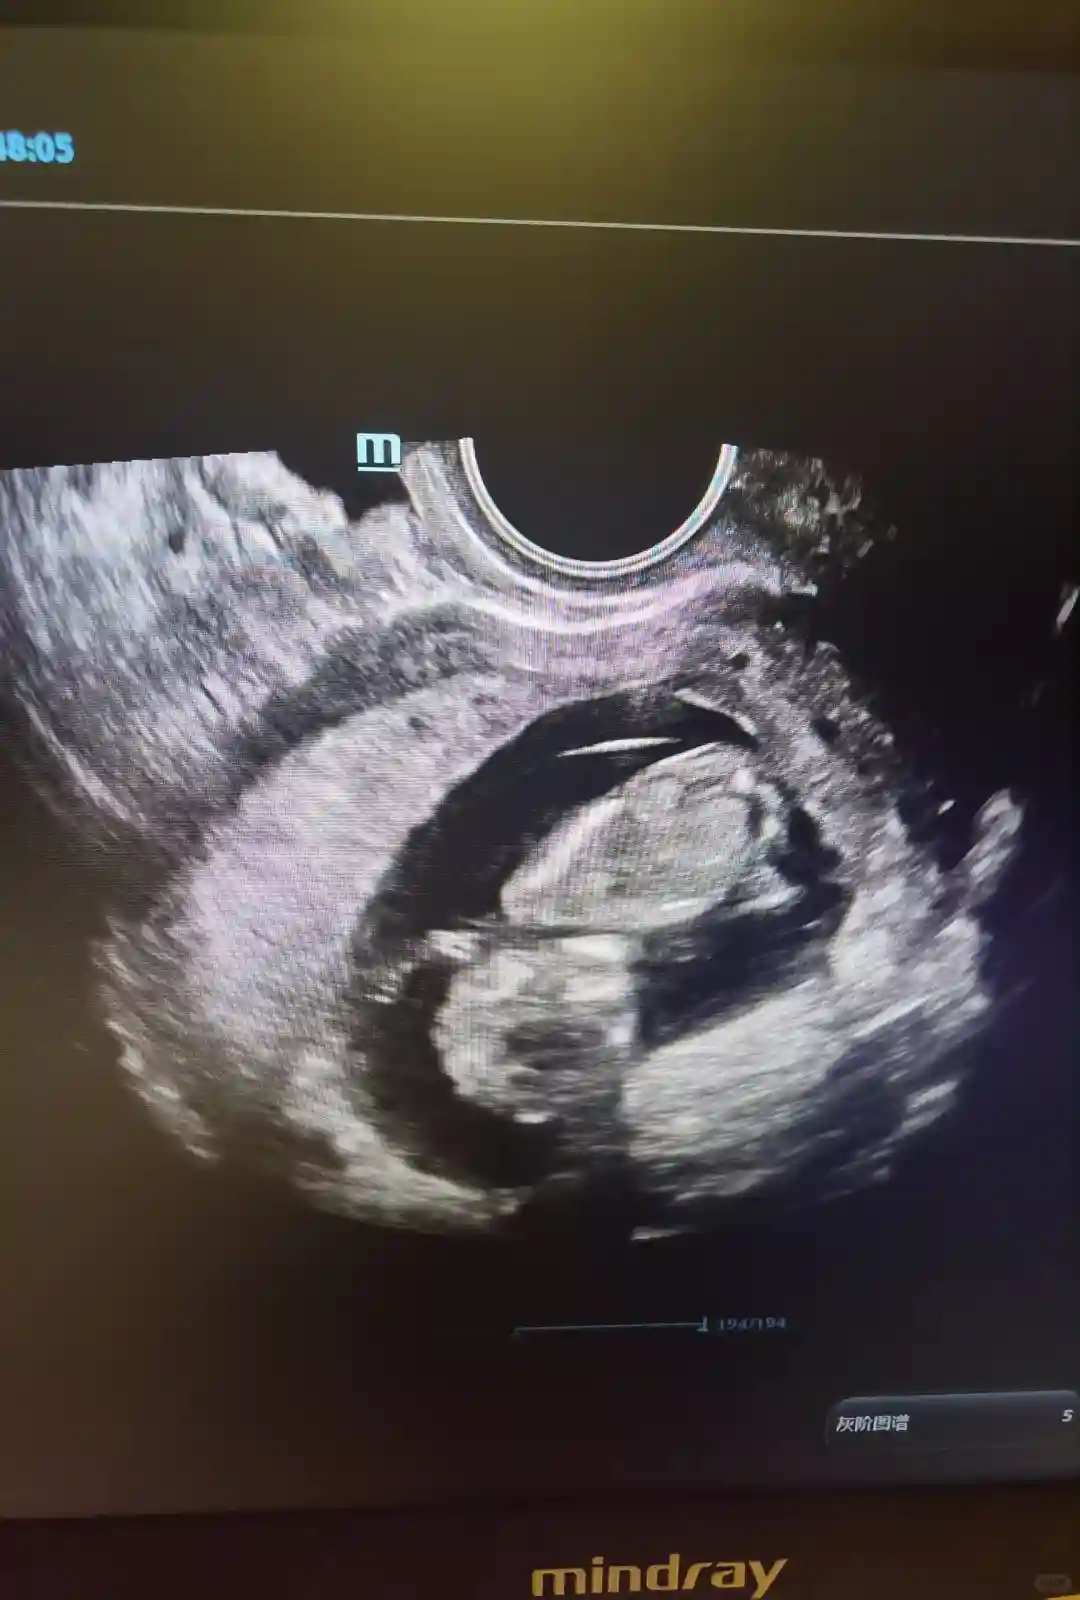

到2024年12月 移植后二超顺利通过,生殖科宣告毕业

第二次移植 我终于迎来了我的宝贝 也顺利通过二超